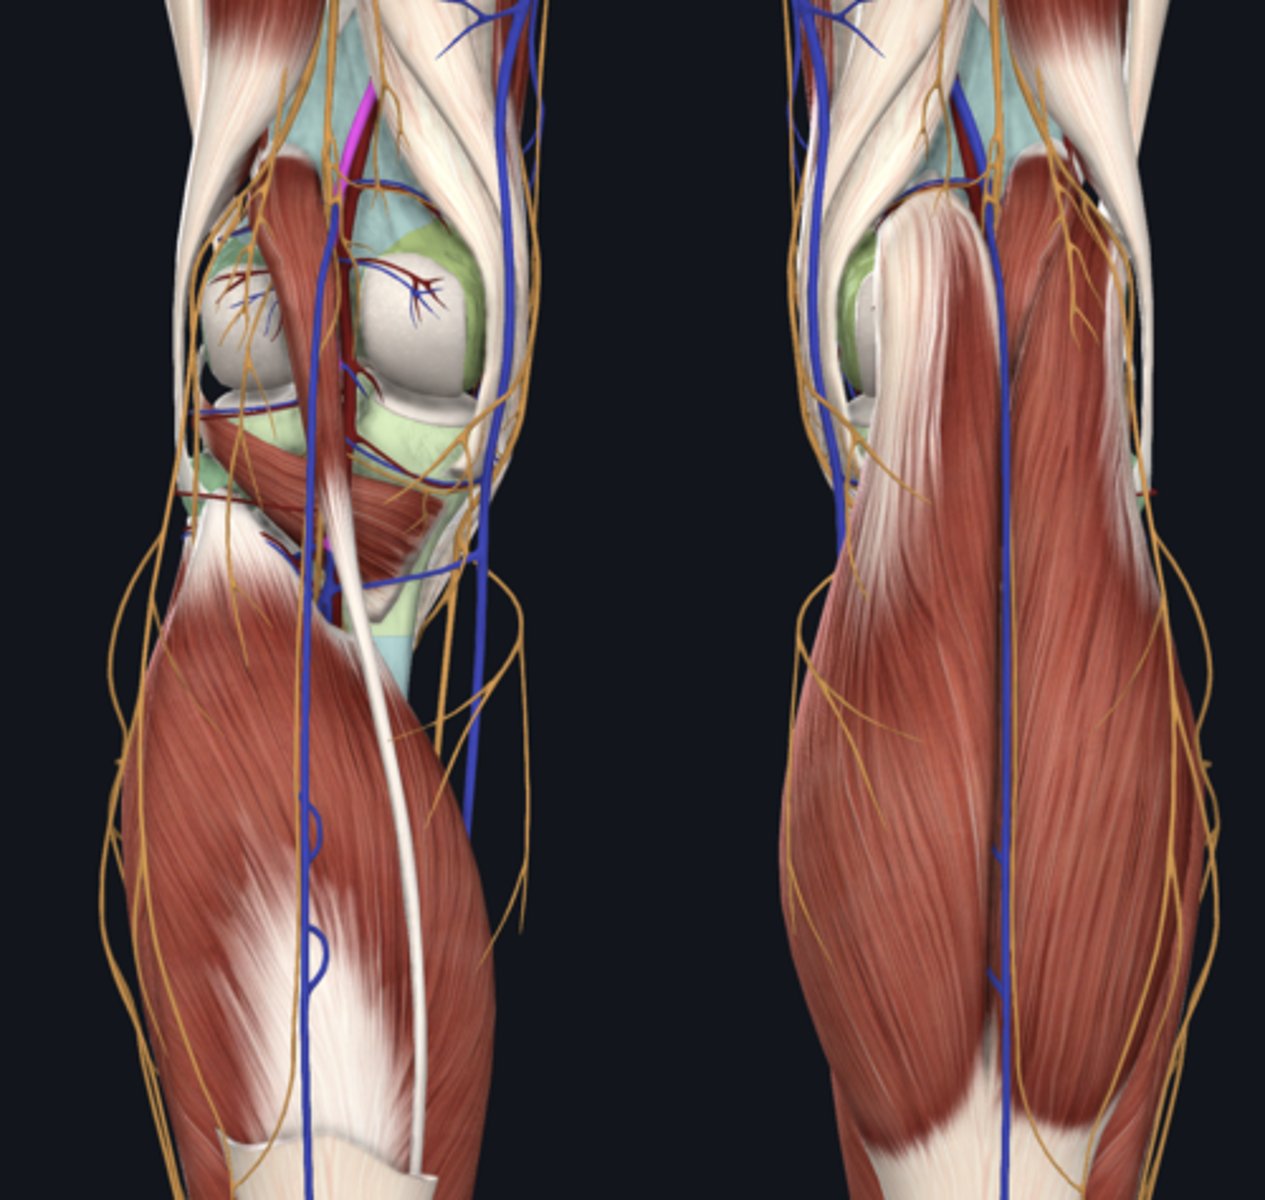

Popliteal artery

artery

Popliteal vein

vein

Tibial nerve

nerve

Common fibular nerve

nerve highlighted in pink

Medial head of gastrocnemius

Lateral head of gastrocnemius

Soleus

Plantaris